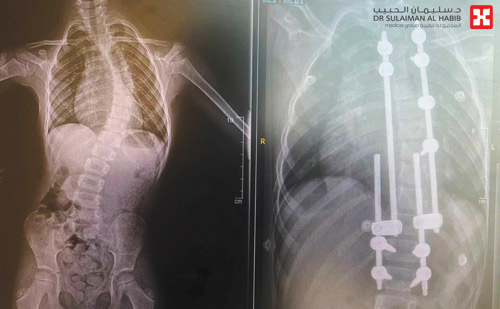

نجح مستشفى الدكتور سليمان الحبيب بالفيحاء في جدة، بإجراء عملية جراحية نوعية لتعديل انحراف بالعمود الفقري «جنف» لطفلة عمرها «4» سنوات، باستخدام أسياخ متطورة وقابلة للتمدد مع نمو الطفل وازدياد طوله مستقبلاً، وأنهت العملية معاناة الطفلة مع مجموعة أعراض أثرت على شكلها ومظهرها، وجنبتها الكثير من المضاعفات الخطرة.

واستطرد قائلاً إن الطفلة أجريت لها عدة فحوصات دقيقة، حيث بينت أشعة الرنين المغناطيسي M.R.I، والفحص السريري، إصابتها بانحراف في الفقرات الـصدرية. وقد أجري لها عملية جراحية، تم فيها تقويم العمود الفقري بهذه التقنية المتقدمة، مع استخدام أجهزة حديثة كمراقبة الأعصاب أثناء الجراحة، وتكللت جهود الفريق الطبي -ولله الحمد- بالنجاح التام، إذ استطاعت الطفلة المشي في نفس اليوم واستردت المظهر الطبيعي، وبعد «4» أيام غادرت المستشفى بحالة صحية جيدة.